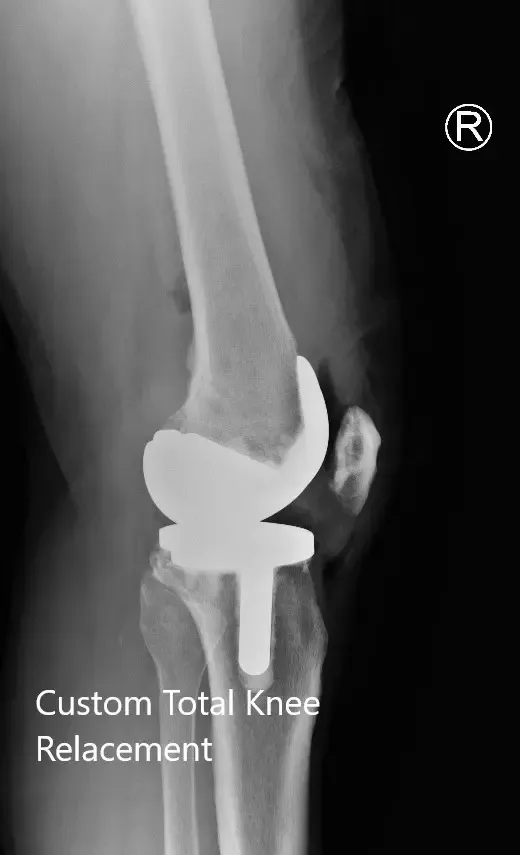

IMPLANTS USED: Custom femoral implant with a tibial tray with 6-mm polyethylene inserts on the right side with 29-mm patellar component. Custom femoral implant with a custom tibial tray with 6-mm polyethylene inserts on the left side with the 32-mm patellar implant.

Postoperative X-ray showing the lateral views of both knees.

Postoperative X-ray showing the AP view of both knees.